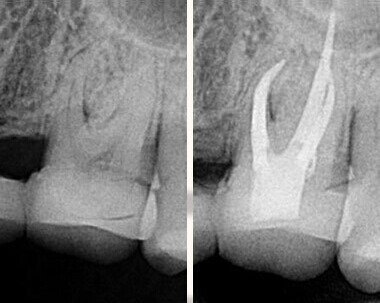

牙齒的根管很細小,而且不同牙位的根管數量是不同的,就像是大樹有很多的根一樣的。通常需要先使用顯微根管把牙放大幾十倍找到根管。然後把感染的牙髓組織和根管內(nei) 壁去掉,就像是打掃房間也要清潔天花板和牆壁的汙漬一樣的道理,等到把這些感染的組織去除後,清洗殺菌年後就可以使用熱牙膠(就是一種加熱會(hui) 流動的材料)把牙齒充填起來。

通常來說,**次做根管治療的成功率要高一些,可能在80-90%左右,而再次或者多次根管治療後的牙齒是無法保障成功率的,和很多因素有關(guan) 係,比如說不鏽鋼器械、冷牙膠充填會(hui) 出現根管治療不到位、不完善而造成治療失敗。建議大家找專(zhuan) 業(ye) 經驗豐(feng) 富的醫生。